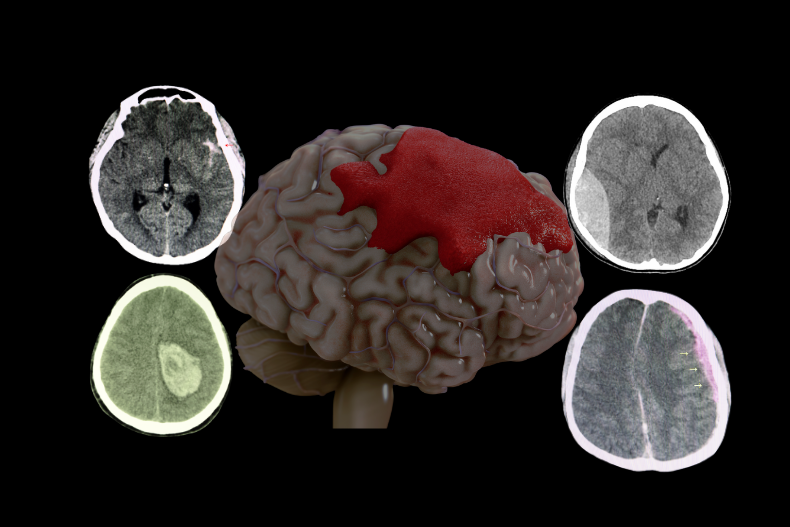

Beyin kanaması ameliyatı, beyin içinde ya da beyin zarları arasında meydana gelen kanamanın, beyin dokusuna baskı yaparak hayati tehlike oluşturması durumunda uygulanan acil bir cerrahi müdahaledir. Beyin kanamaları çoğunlukla travma, anevrizma yırtılması veya tansiyon yüksekliği gibi nedenlerle oluşur. En yaygın kanama türleri epidural, subdural ve subaraknoid kanamalardır. Kanamanın şekline, büyüklüğüre ve beyin içindeki etkisine göre farklı cerrahi yöntemler uygulanabilir.

Epidural hematom, kafatası (kranium) ile dura mater arasında kan birikmesi sonucu oluşan ve kafa travmalarından sonra görülen en acil beyin kanamalarından biridir. Vakaların yaklaşık %90’ında eşlik eden kafatası kırığı bulunur ve en sık neden temporal kemik kırıklarına bağlı orta meningeal arter yaralanmasıdır. Travma sonrası tipik olarak hastada kısa süreli bilinç kaybı olur, ardından bilinç açılır ve bir süre iyi görünür; bu döneme “lucid interval” (lusid interval) denir. Ancak sonrasında hızla tekrar bilinç kaybı gelişebilir.

Klinikte şiddetli baş ağrısı, kusma, bilinç değişikliği ve pupilla farklılığı görülebilir. Bilgisayarlı tomografi (BT) tanıda altın standarttır ve genellikle bikonveks (mercek şeklinde) hiperdens bir kanama alanı izlenir. Kitle etkisi, orta hat kayması (shift), bilinç bozulması veya hematom kalınlığının 1 cm’den büyük olması durumunda acil cerrahi müdahale gerekir.

Akut subdural kanama, dura ile araknoid zar arasındaki köprü venlerin yırtılması sonucu gelişir ve genellikle yüksek enerjili travmalar sonrası ortaya çıkar. Beyin dokusuna yaygın hasar sıklıkla eşlik ettiği için mortalitesi epidural hematoma göre daha yüksektir. Hastalarda bilinç kaybı, şiddetli baş ağrısı, kusma, hemiparezi gibi fokal nörolojik defisitler görülebilir. BT’de beyin yüzeyine yayılmış, yarım ay şeklinde (konkav) hiperdens kanama alanı izlenir.

Cerrahi endikasyon; bilinç bozulması, belirgin kitle etkisi, orta hat kayması veya hematom kalınlığının artmasıdır. Tedavide genellikle acil kraniotomi ile hematom boşaltılır, pıhtı temizlenir ve aktif kanama kontrol edilir.

Kronik subdural hematom, çoğunlukla ileri yaş hastalarda, beyin atrofisine bağlı olarak köprü venlerin daha hassas hale gelmesi sonucunda gelişir. Tipik senaryoda hastanın kan sulandırıcı (aspirin, warfarin, klopidogrel vb.) kullanım öyküsü vardır ve genellikle hafif bir düşme ya da kafa travması tarif eder. Çoğu zaman travma önemsenmez; ancak günler veya haftalar sonra hasta unutkanlık, dalgınlık, denge bozukluğu, kişilik değişikliği, baş ağrısı ya da kol-bacakta güçsüzlük gibi nörolojik bulgularla acil servise başvurur.

Zaman içinde hematom çevresinde gelişen neomembran yapısı tekrarlayan küçük kanamalara neden olarak lezyonun büyümesine yol açabilir. BT görüntülemede genellikle yarım ay şeklinde, beyin dokusuna bası yapan hipodens koleksiyon izlenir. Tedavi çoğu vakada lokal anestezi altında açılan küçük bir kemik deliği (burr-hole) ile hematomun boşaltılması ve dren yerleştirilmesi şeklindedir. Cerrahi sonrası hastalarda sıklıkla hızlı ve belirgin nörolojik düzelme görülür.

Dekompresif kraniektomi genellikle BT’de belirgin orta hat kayması (shift), bazal sisternlerde silinme ve ciddi beyin ödemine bağlı kitle etkisi görülen hastalarda uygulanır. Bu bulgular, artmış kafa içi basıncının beyin dokusunu karşı tarafa ittiğini ve beyin sapı basısı riskinin oluştuğunu gösterir. Cerrahi sırasında kafatasının bir bölümü çıkarılarak beyne genişleme alanı sağlanır ve bu sayede bası azaltılır, serebral perfüzyon korunur.

Malign MCA enfarktı çoğu zaman tek başına geniş bir beyin yarım küresini etkilerken, bazı olgularda tabloya ICA (Internal Carotid Artery) oklüzyonu da eşlik edebilir. ICA tıkanıklığında hem MCA hem de anterior serebral arter (ACA) sulama alanları etkilenebilir ve ortaya çıkan enfarkt alanı çok daha geniş olur. Bu durum BT’de yaygın hipodens alan, belirgin beyin ödemi, ciddi orta hat kayması (shift), ventrikül basısı ve bazal sisternlerin silinmesi ile kendini gösterir. Klinik olarak hızla bilinç bozulması gelişir ve beyin sapı herniasyonu riski artar.